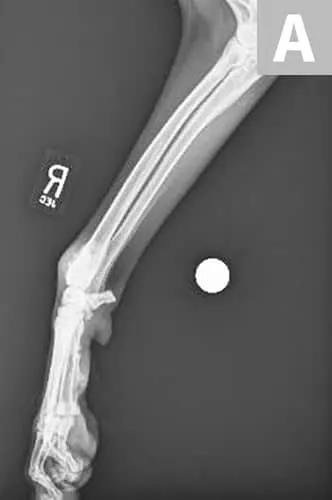

(A) Radiograph of a distal radial osteosarcoma. Centered at the distal metaphysis of the radius, there is evidence of permeative and moth-eaten lysis. There is also concurrent ill-defined periosteal proliferation consistent with an aggressive bone lesion. (B) CT scan of distal radial osteosarcoma in the same patient. Coronal view of limb in bone window. There is more evidence of geographic bone lysis and evidence of periosteal proliferation. Consistent with an aggressive bone lesion. (C) Bone scan of the distal radial osteosarcoma in the same patient. Note the increased uptake of radiopharmaceutical in the distal radius of the patient (arrow).